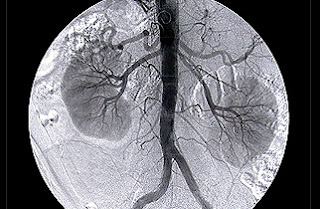

Cánula farmacoactiva que libera el medicamento tacrolimus. Foto: Armando Pérez de Prado.